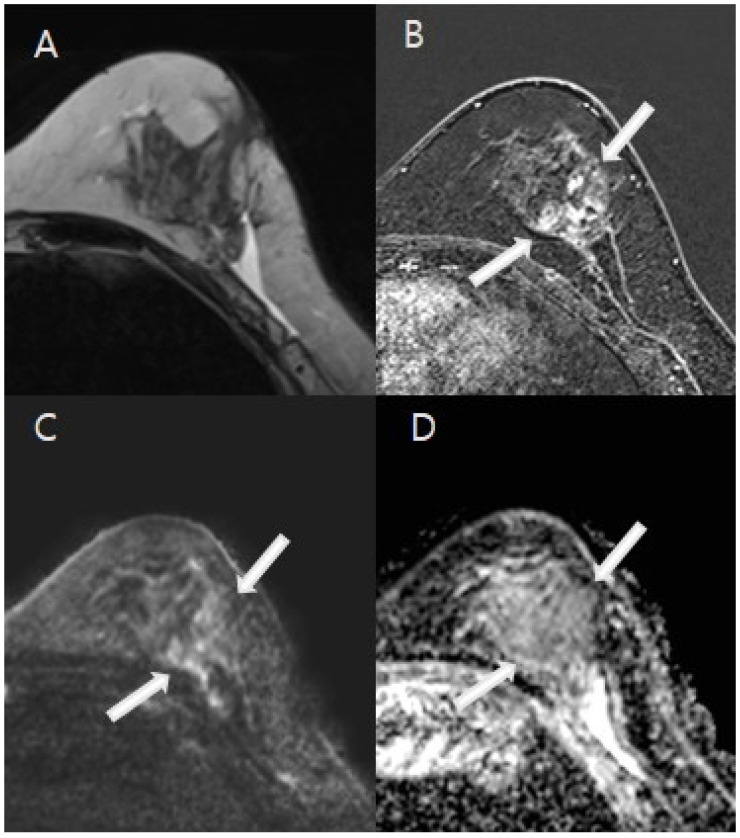

Objectives: To evaluate the effectiveness of breast MRI, including diffusion-weighted imaging (DWI), in detecting residual lesions in patients with malignancy after excisional biopsy.

Methods: From January 2018 to December 2023, 3T breast MRI was performed to assess lesion morphology, residual size, and enhancement kinetics. The apparent diffusion coefficient (ADC) values were measured, and the diagnostic outcomes of CE-MRI, CE-MRI with DWI, mammography (MG), and ultrasound (US) were compared with clinical and histopathological data.

Results: A total of 152 lesions were analyzed, with 36.2% showing residual malignancy. Both CE-MRI and CE-MRI with DWI effectively identified residual lesions, with significant differences in morphology, size, kinetic patterns, and ADC values (all p < 0.001). CE-MRI with DWI showed a sensitivity of 90.9% and an NPV of 93.6%, compared with 89.1% sensitivity and 92.2% NPV for CE-MRI alone. Sensitivities for MG and US were 57.1% and 38.7%, with NPVs of 64.7% and 59.6%, respectively. Diagnostic accuracy was highest for CE-MRI with DWI (80.9%), followed by CE-MRI (79.0%), MG (60.3%), and US (59.7%). The AUC for CE-MRI with DWI (0.831) was slightly higher than CE-MRI alone (0.811), though not significant (p = 0.095). AUCs for MG and US were lower at 0.623 and 0.563, with no significant difference between MG and US (p = 0.234).

Conclusions: CE-MRI with DWI and CE-MRI alone were comparable and demonstrated excellent performance in discriminating between women with and without residual disease. Integrating CE-MRI with DWI could become a standard protocol for patients with suspected residual malignancy after excisional biopsy.